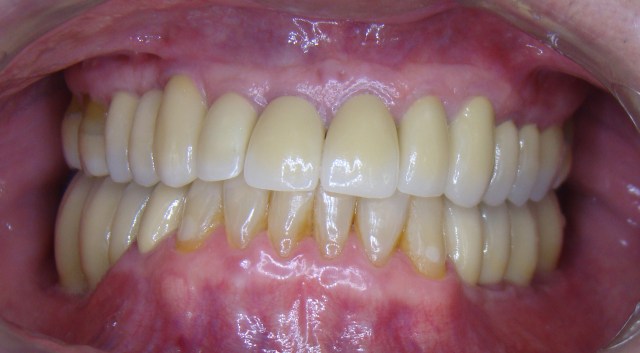

» Caso 7 - Implantes dentários e reabilitação complexa

Neste caso a paciente apresentou a necessidade de remoção de todos os dentes natur...